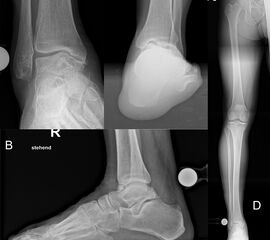

Native Röntgenaufnahmen des Sprunggelenks in 2 Ebenen unter Belastung (antero-posterior und lateral) erlauben Gelenkspaltverschmälerung, osteophytäre Anbauten sowie Achsfehlstellungen zu beurteilen. Eine „Canale-Aufnahme“ (Pronation des Fußes von ca. 15 °, Röntgenstrahl 75 ° nach kranial) 9 kann hilfreich sein, die subchondralen Oberflächen einzusehen. Die korrekte Abbildung der Sprunggelenkgabel in der sogenannten „Gabel-Aufnahme“ (mortise-view) ist zudem notwendig zur Beurteilung der Gelenkkongruenz. An Grenzen stößt die konventionelle Röntgenaufnahme allerdings bei OCLs ohne weitere knöcherne Veränderungen. Bis zu 50% der OCLs sind auf konventionellen Röntgenaufnahmen nicht sichtbar. Auch kann der Zustand des Knorpels nicht beurteilt werden 10. Bei Achsfehlstellungen werden zusätzlich Rückfußachs-Aufnahmen (Saltzman View) angefertigt bzw. eine Einbeinstandaufnahme zur Bestimmung der Becken-Bein-Achse.

Zur Vollansicht und zum Lesen der Bildbeschreibung bitte das Bild anklicken.